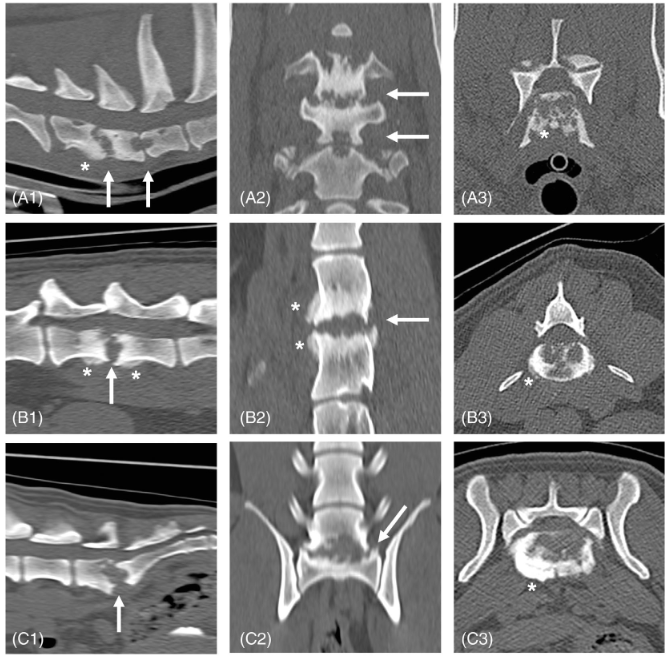

discospondylitis 가 있는 개의 CT 소견

대략적으로 심한 양상으로 관찰되는 병변이 위와 같으며 종양성 골융해와 감별이 필요한데 핵심적인것이 주변의 연부조직 밀도의 종괴 병변과 부종과의 감별이 핵심 포인트.

incidental로 관찰되는 경우도 많으니 CT 의뢰를 하는 경우 반드시 기억해 둘 소견